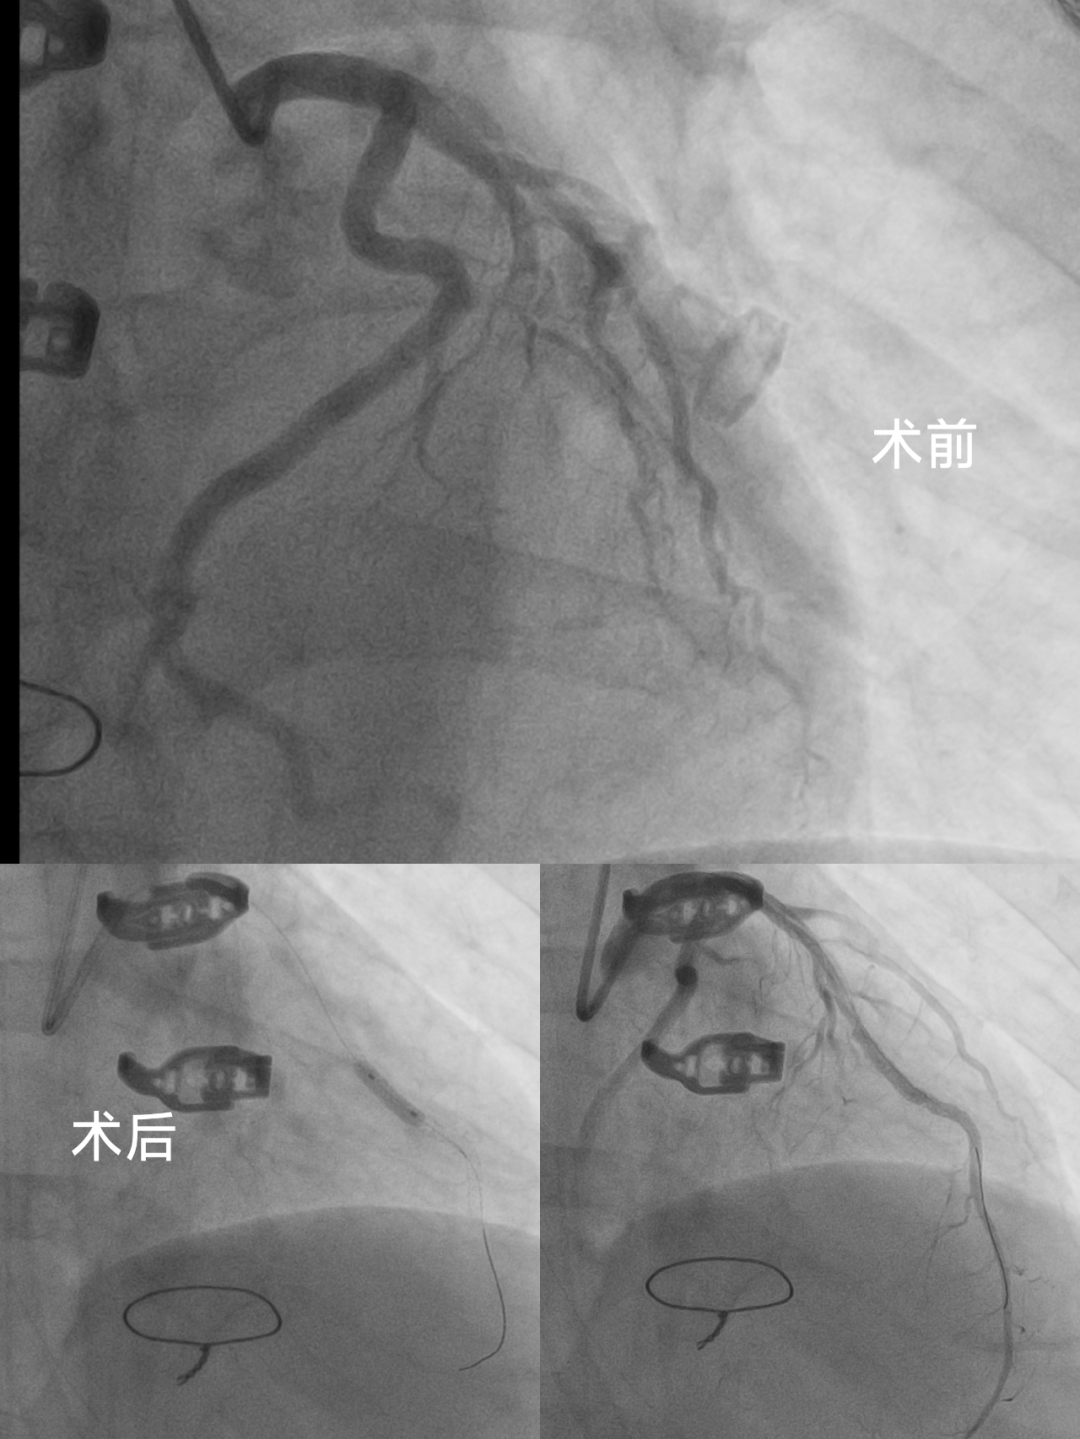

峰回路轉(zhuǎn),再戰(zhàn)冠脈

術(shù)后,繆先生的狀況依舊嚴峻。即便在 ECMO 和 IABP 的支持下,他的血流動力學(xué)仍不穩(wěn)定,心電圖和心肌酶顯示存在心肌缺血現(xiàn)象。面對這一復(fù)雜情況,心臟大血管外科胡名松主任醫(yī)師、李君副主任醫(yī)師,CCU 廖火城主任醫(yī)師、桑云華副主任醫(yī)師等專家再次商討,決定立即為繆先生施行冠狀動脈造影加支架植入手術(shù)。手術(shù)成效顯著,繆先生終于脫離生命危險。